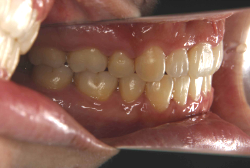

「出っ歯を治したい」という主訴で来院したケースです。診断の結果、「2級1類の上顎前突+軽度叢生」と判明しました。2級というのは、基本的に出っ歯の噛み合わせになっていることを言います。その中でも上の前歯が著しく外に反っているケースを、「1類」といいます。初診時の横向きの写真を見ると、それがはっきり分かります。上の前歯に押されて唇も膨らんで、審美線をかなりオーバーしています(審美線とは、鼻の先端と顎の先端を結ぶ線のことで、この線よりも唇は内側にある方が良いとされています)。

このような症状の場合は、前歯を内側に入れるためにかなり大量の隙間を必要とします。通常は上下左右の小臼歯を抜歯させていただくのが正解です。治療後は歯の角度が正しくなっただけでなく、唇の審美性が大幅に改善しました。もちろん噛み合わせ的にも正しい状態が確立しています。